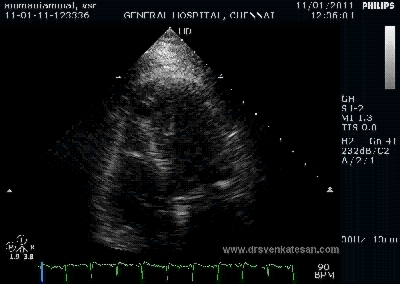

Here is 55 year old women came with extensive anterior MI with lower septal rupture.(She belonged to type 3 of the above scheme)

)

Note the septal rupture is visible even in 2D Echo

Color flow showing significant shunting from LV to RV.This shunt depends upon the LV contractile function, LVEDP and ofcourse the RV pressure

If there is severe RV dysfunction or bi ventricular dysfunction flow across the defect is inconspicuous.Brisk left to right shunting may be an indirect marker for good LV systolic function and absence of significant pulmonary hypertension.Both imply a better outcome.

The main determinant  of survival is the  underlying LV dysfunction and associated co morbidity(Renal function ) and complications .